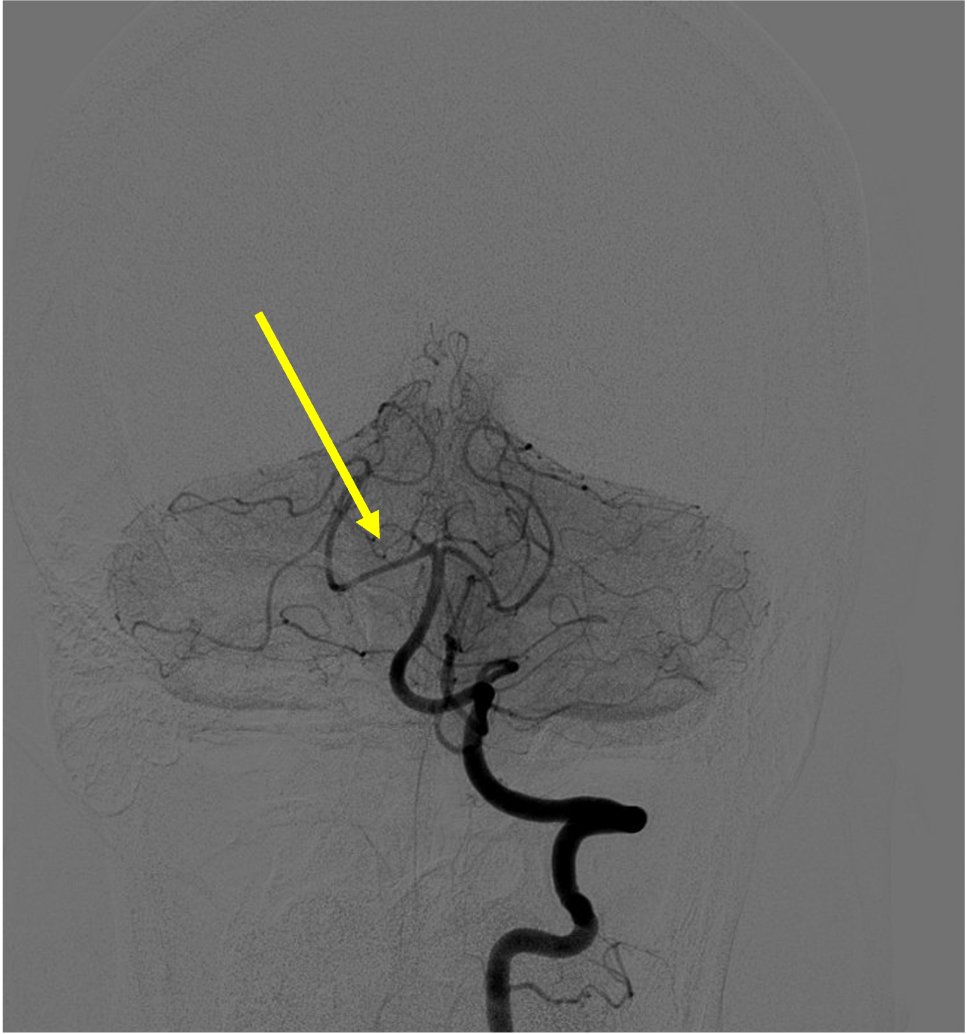

Pathologic early filling of this structure is seen on this AP view of the R CCA injection:

Cavernous sinus